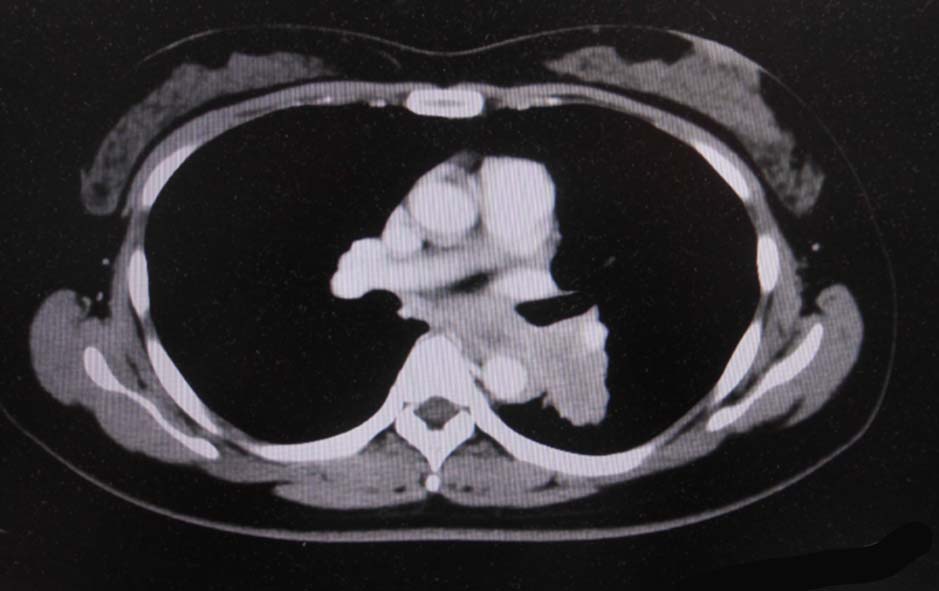

当院を受診する4か月前から前胸部違和感を自覚していた. 2か月前から喘鳴を伴う咳嗽があり近医を受診.気管支喘息が疑われ加療されたが症状は改善しなかった.

経過観察中に施行された胸部CTでは左肺癌が疑われた.精査加療目的に当院呼吸器内科を紹介受診.

血液検査:腫瘍マーカー cytokeratin 19の上昇あり[14 (>3.5ng/mL)],ProGRP, CEA, CA19-9の上昇なし

CT画像:左肺から縦隔に及ぶ腫瘍(肺は単独病変. 肺内転移なし.),乳腺腫瘤,子宮腫瘤, 多発肝腫瘤あり.

CT画像および肺腫瘤生検組織